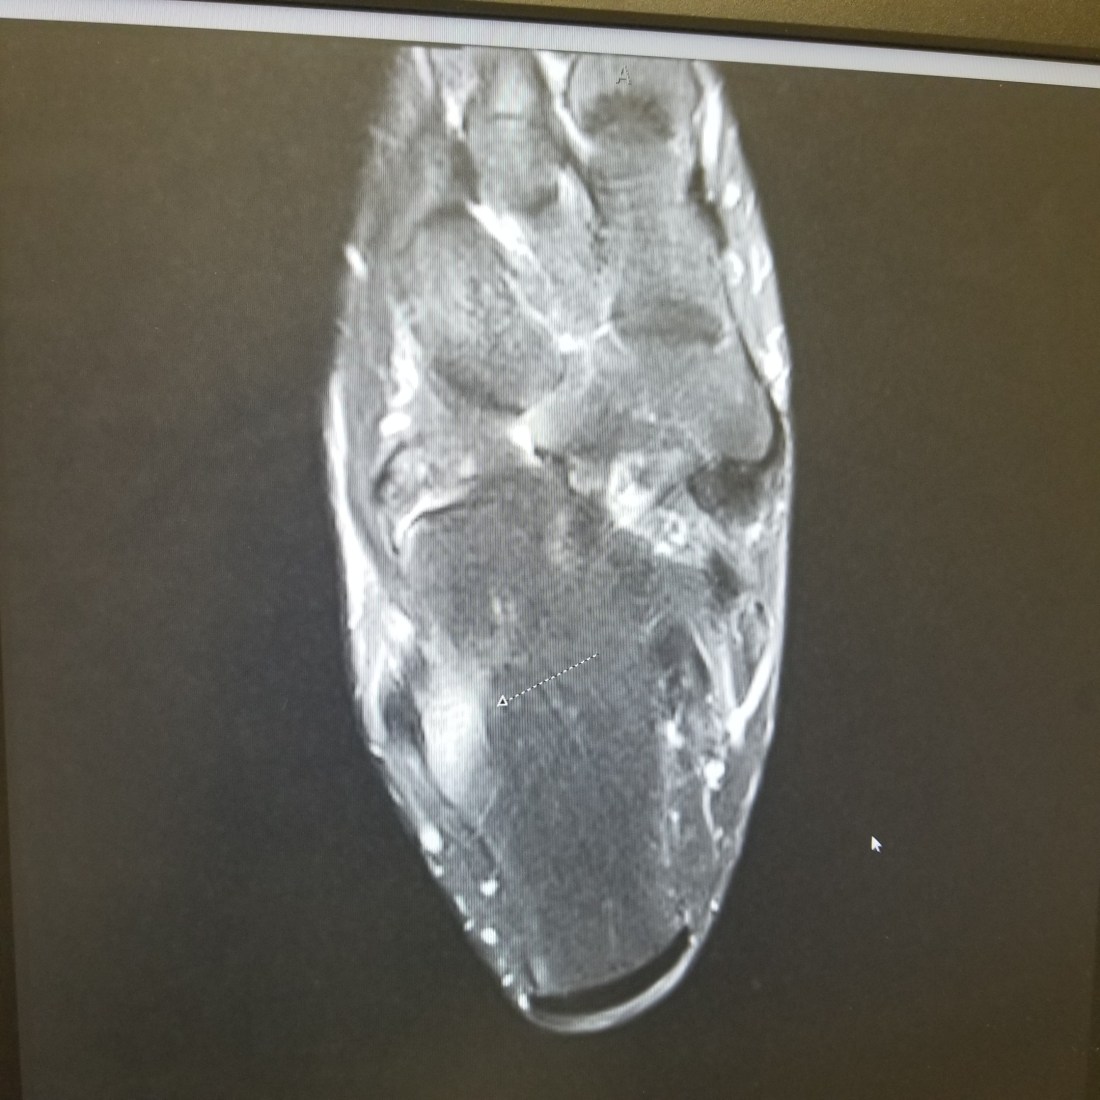

I walked outside 3 days in a row the week I came back in town. The third day the pain started. By September I’m emailing the doctor whining and she advised me to put the braces back on and to get an MRI. I wore the braces for about 5 days and stopped. This was yet another mistake.

My follow-up showed the nastiness I did not want to see, a contusion, inflammation and arthritis. The issue was the former two, note the latter. I asked what’s next? She tried to be easy but kept it real. A boot, crutches and another contraption to even my gait, RICE, NSAIDS and the same no-exercise regimen except for the pool or a rower.